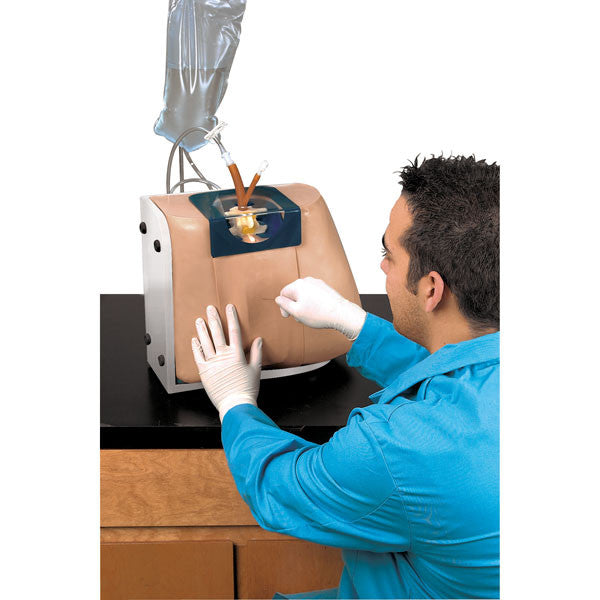

Epidural Injection Trainers

Train students and healthcare professionals in essential epidural injection skills using our highly realistic spine simulators, designed to enhance clinical training and procedural accuracy.

Our range of epidural injection trainers includes detailed anatomical models that replicate the lumbar and thoracic spine, providing a hands-on learning experience for anaesthetists, medical students, and pain management specialists. These advanced simulators allow users to practise needle placement, identify key anatomical landmarks, and develop proficiency in administering epidural and spinal anaesthesia with confidence. Ideal for medical schools, hospitals, and professional training programmes, these epidural trainers support skill development in regional anaesthesia, labour pain management, and spinal procedures. With lifelike materials that simulate real patient responses, our models offer a realistic and immersive training experience.